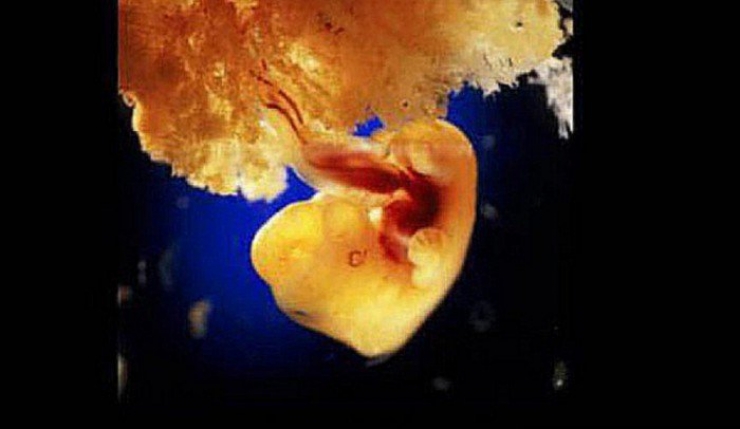

8: L'embryon en plein développement après 22 jours. La zone grise deviendra le cerveau

9: Au bout du 28ème jour de développement, le coeur du foetus commence à battre

10: 28 jours après la fécondation le foetus ressemble à cela